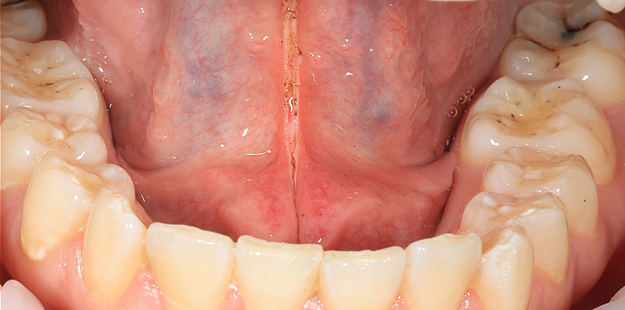

Красивая и аккуратная работа, по пластике уздечки языка. Короткая уздечка сильно ограничивает положение и движение языка. Процедура проведена диодным хирургическим лазером, быстро и безболезненно.

До лечения